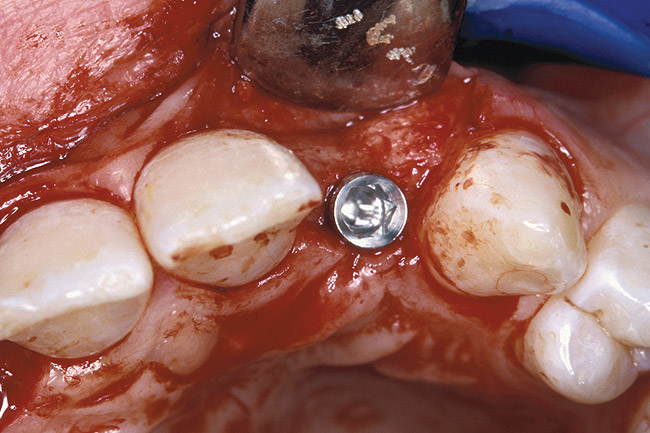

Before the day of surgery, the patient was seen by the orthodontist for the removal of the orthodontic brackets. The patient still was not pleased with the position of the two centrals, and it was determined that this would be addressed after implant placement (Figure 26). The anatomical variations of the crestal tissue and lack of interdental papilla can be appreciated in the close-up views of the right and left sites (Figure 27 and Figure 28). There were no surprises on the day of surgery as all of the decisions were made during the planning phase, before the scalpel ever touched the patient. The occlusal view of the CT 3D model revealed the wider alveolar ridge on the right side and thinner crest on the left side (Figure 29). This was confirmed when the full-thickness mucoperiosteal flaps were elevated, and the underlying bone revealed (Figure 30). The tooth-borne templates were designed to facilitate the drills and drilling sequence specific to the diameters of the predetermined implants (Figure 31). Each template contained an embedded 5-mm long stainless steel tube, which was approximately 0.2-mm wider than each drill (just wide enough to allow for the drills to rotate freely). Once positioned over the natural teeth, the template was secure and offered precision accuracy in transferring the implant locations from the original software-designed plan, allowing the potential for internal and external irrigation (Figure 32).

The 3.7-mm diameter Tapered Screw-Vent implant drilling sequence requires three drills: pilot, intermediate, and final sizing. Thus, three separate templates were fabricated to accommodate these sizes. The templates were removed easily and replaced with the next sequential size in less time than it takes to change the drill on the surgical handpiece. After the osteotomies had been completed, the implants were delivered to the site (Figure 33 and Figure 34). For this internal hex connection implant, the author recommends that the flat of the anti-rotational hex be positioned to the facial for proper orientation of the restorative components (Figure 35). Pre-prepared margins were created from a milled titanium fixture mount transfer post, which was delivered to the implant as support for an immediate transitional restoration. The facial “dot” helped to confirm the orientation of the abutment to the facially positioned flat side of the internal hex connection (Figure 36). Before cementation of the transitional acrylic restorations, a closed-tray, fixture-level impression was made, and a soft-tissue model was fabricated.

Figure 29  VIRTUAL PLANNING AND SURGERY The information gained from the 3D model was confirmed when the flaps were elevated.

Figure 29

Figure 30  VIRTUAL PLANNING AND SURGERY The information gained from the 3D model was confirmed when the flaps were elevated.

Figure 30

Figure 31  VIRTUAL PLANNING AND SURGERY A surgical template was derived from the final treatment plan created in the software, which facilitated the drilling sequence and precise location of placement.

Figure 31

Figure 32  VIRTUAL PLANNING AND SURGERY A surgical template was derived from the final treatment plan created in the software, which facilitated the drilling sequence and precise location of placement.

Figure 32